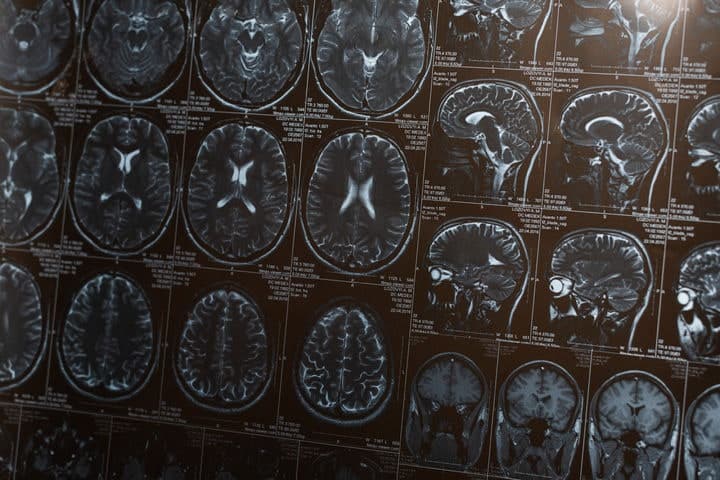

“뇌졸중 후 신경세포 죽이는 경로 찾았다”…韓연구진, 골든타임 16배 늘릴 신약 개발

뇌졸중 발생 시 별세포가 과산화수소와 콜라겐을 생성하여 신경세포를 죽입니다.

신약후보물질 KDS12025는 골든타임을 2일로 늘려 쥐와 영장류의 운동능력을 회복시켰습니다.